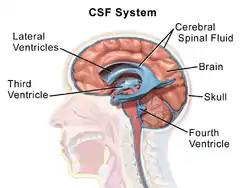

Cerebrospinal fluid is a clear, colourless transcellular fluid that circulates around the brain in the subarachnoid space, in the ventricular system, and in the central canal of the spinal cord. It also fills some gaps in the subarachnoid space, known as subarachnoid cisterns.[47] The four ventricles, two lateral, a third, and a fourth ventricle, all contain a choroid plexus that produces cerebrospinal fluid.[48] The third ventricle lies in the midline and is connected to the lateral ventricles.[47] A single duct, the cerebral aqueduct between the pons and the cerebellum, connects the third ventricle to the fourth ventricle.[49] Three separate openings, the middle and two lateral apertures, drain the cerebrospinal fluid from the fourth ventricle to the cisterna magna, one of the major cisterns. From here, cerebrospinal fluid circulates around the brain and spinal cord in the subarachnoid space, between the arachnoid mater and pia mater.[47] At any one time, there is about 150mL of cerebrospinal fluid – most within the subarachnoid space. It is constantly being regenerated and absorbed, and is replaced about once every 5–6 hours.[47]

A glymphatic system has been described[50][51][52] as the lymphatic drainage system of the brain. The brain-wide glymphatic pathway includes drainage routes from the cerebrospinal fluid, and from the meningeal lymphatic vessels that are associated with the dural sinuses, and run alongside the cerebral blood vessels.[53][54] The pathway drains interstitial fluid from the tissue of the brain.[54]